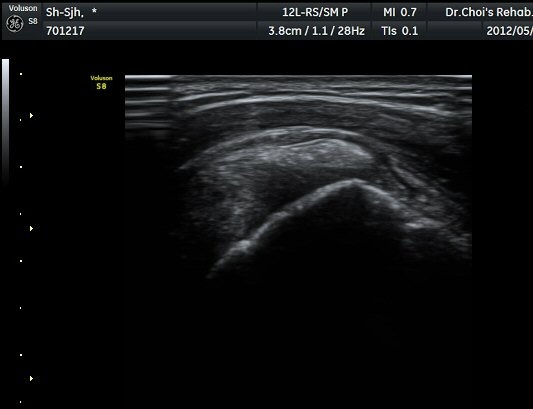

°Ë»ç¿¡¼­ Ç÷·ùÁõ°¡°¡ °üÂûµÈ´Ù(»çÁø 2). À̵ιڱ٠Á¾´Ü¸é°Ë»ç¿¡¼­µµ °Ç ÁÖÀ§ ¼ö¾×Àú·ù°¡ È®ÀÎ

µÈ´Ù(»çÁø 3). ±Ø»ó°Ç Á¾´Ü¸é°Ë»ç»ó ±Ø»ó°Ç ºÎÂøºÎ¿¡ °í¿¡ÄÚ µ¢¾î¸®°¡ °üÂûµÇ°í(»çÁø 4, 5)

ÆÄ¿öµµÇ÷¯ °Ë»ç¿¡¼­ Ç÷·ùÁõ°¡¸¦ º¸ÀδÙ(»çÁø 6).  Ⱦ´Ü¸é°Ë»ç¿¡¼­µµ °í¿¡ÄÚ µ¢¾î¸®¿Í